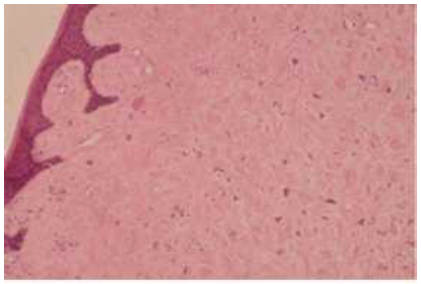

The patient had poor oral hygiene and was not taking any medication. There were no systemic diseases and her medical history was noncontributory. The lesion was first noticed by the patient 3 years earlier and it had slowly grown to its present size. Neither radiopacities within the lesion nor radiolucency of the underlying bone were observed from the periapical radiographic evaluation. The differential diagnosis included peripheral ossifying fibroma, peripheral giant cell granuloma, and GCF. Routine blood tests were found normal. Complete surgical excision of the lesion was performed using a number 11 scalpel blade under local anesthesia and strict aseptic protocol and the specimen was submitted for histopathologic analysis. Calculus was not associated to neighbor teeth so that treatment of their surface was not necessary. Tissue examination under optical microscopy revealed a lesion composed of mature and compact fibrous connective tissue with numerous large spindle- and stellate-shaped mononuclear cells, and some multinucleated cells covered by a stratified squamous epithelium with thin, papillary projections (Fig. 2). The stellate-shaped giant cells had hyperchromatic nuclei, while the cytoplasm was well-demarcated and the cells frequently had a dendritic-like process (Fig. 3). Areas of inflammation were rarely noted. The diagnosis of GCF was made. No complications or recurrence of the lesion have been noted after 4 years of follow-up.

The clinical and histopathologic characteristics of the excised lesion were in agreement with the existing descriptions of GCFs in the literature; specifically, a bosselated, peduncunlated exophytic mass largely composed of fibrous connective tissue loosely arranged with a prominent vascular element, especially in the subepithelial zone. The most characteristic histologic feature is the presence of large spindle-shaped or more often stellate-shaped cells. These cells are usually mononuclear but multinucleated cells can also be present. The cytoplasm of these cells is well-demarcated and occasional dendritic processes are observed. The cellular boundaries appear to be separated from the surrounding collagen fibers in areas, and some of the cells contain melanin granules.12 The stellate-shaped cells are most prominent just beneath the epithelium and are less common or absent in the central portion of the lesion.3,5